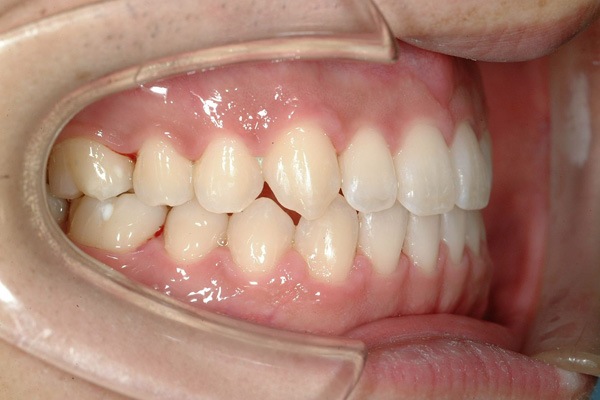

臼歯部における横方向の咬合関係の異常は、上歯列弓の相対的な狭窄が原因で起こる舌側交叉咬合(lingual crossbite)と、下顎に比べ相対的に大きい上顎のために生じた頬側交叉咬合(buccal crossbite)に分けられる。舌側交叉咬合の方が、頬側交叉咬合よりも多い。 また、舌側交叉咬合は片側性交叉咬合と両側性交叉咬合に分類することがあるが、はっきりとした片側性交叉咬合は通常、上歯列の両側性の狭窄と下顎の交叉咬合側への変位を示す。